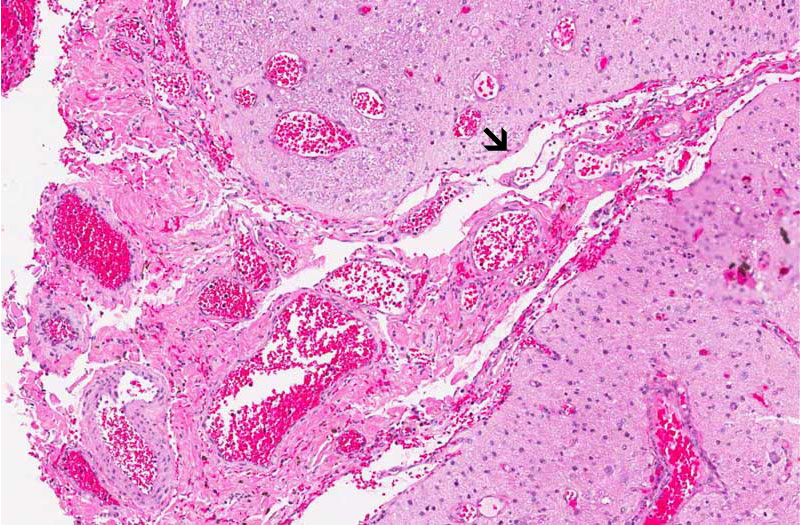

Hematoxylin & eosin

Area 2: There is a rich network of blood vessels attached to the brain parenchyma. The leptomeninges is not readily seen . The border between the blood vessel and the neural parenchyma is well demarcated (arrow). In this particular area, an island of neural parenchymal tissue (n) is trapped in between two portion of fibroconnective tissue with rich vasculature (f).

Area 3: In contrast to Area 2, the blood vessels are not firmly adhered to the brain parenchyma and the leoptmeninges (arrow) can be recognized.